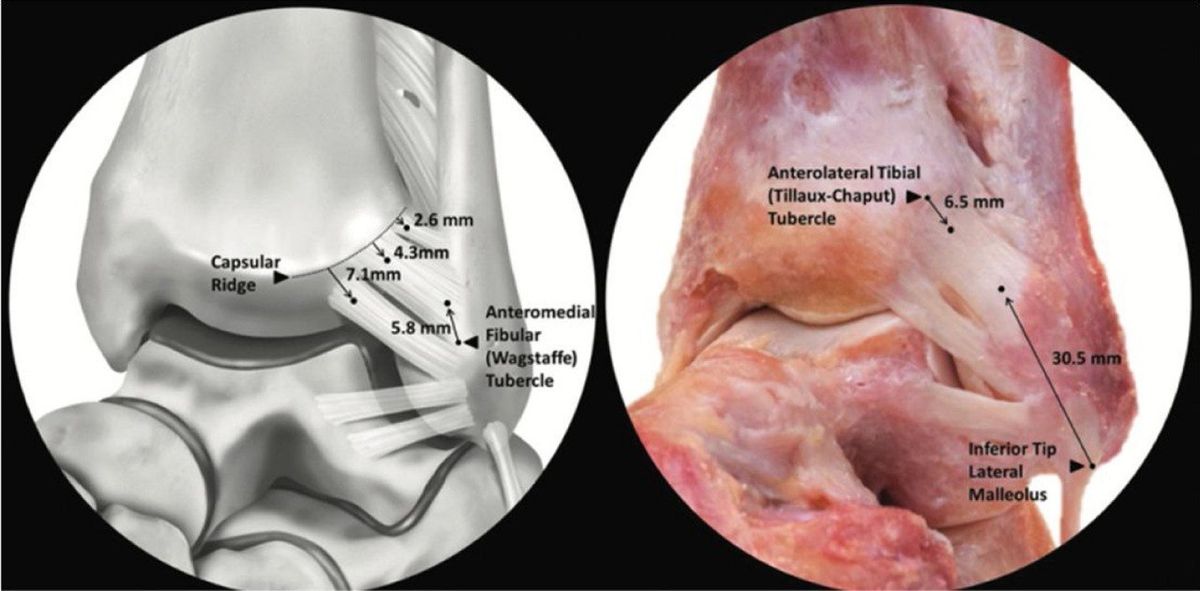

передняя нижняя большеберцово-малоберцовая связка (ПНБМс, AITFL)

ПНБМс проходит косо от переднего бугорка дистальной части большеберцовой кости (фрагмент Тиллау-Шапут), в среднем на 5 мм проксимальнее суставной поверхности, к переднему бугорку дистальной части малоберцовой кости. Связка имеет мультифасцикулярное строение — между пучками коллагеновых волокон расположена жировая ткань.

ПНБМс разделена на три части. Верхняя — самая короткая, начинается чуть проксимальнее переднего бугорка большеберцовой кости и прикрепляется чуть проксимальнее переднего бугорка малоберцовой кости. Средняя — наиболее прочная, проходит между передними бугорками большеберцовой и малоберцовой костей. Нижняя часть — самая длинная, распространяется дистальнее передних бугорков.

Добавочная передняя нижняя большеберцово-малоберцовая связка, известная как связка Бассетта (Bassett’s ligament), определяется в 21–92% случаев при анатомических препарациях и МРТ-исследованиях. Она проходит дистальнее и параллельно ПНБМс, не покрыта синовиальной тканью, является внутрисуставной структурой, пересекает проксимально-латеральный край голеностопного сустава и при тыльном сгибании контактирует с латеральным блоком таранной кости. Именно связка Бассетта может быть причиной переднелатерального импинджмента.

ПНБМс — самая слабая из четырёх синдесмотических связок и первой поддаётся нагрузкам, вызывающим наружную ротацию малоберцовой кости вокруг её продольной оси.

Рис. 7. передняя нижняя большеберцово-малоберцовая связка (ПНБМс/AITFL). 3D-модель и кадаверный препарат. Три пучка связки (Williams et al.). Основной пучок прикрепляется на малоберцовой кости в 30,5 мм от верхушки, на большеберцовой — в 9,3 мм от переднелатерального угла.